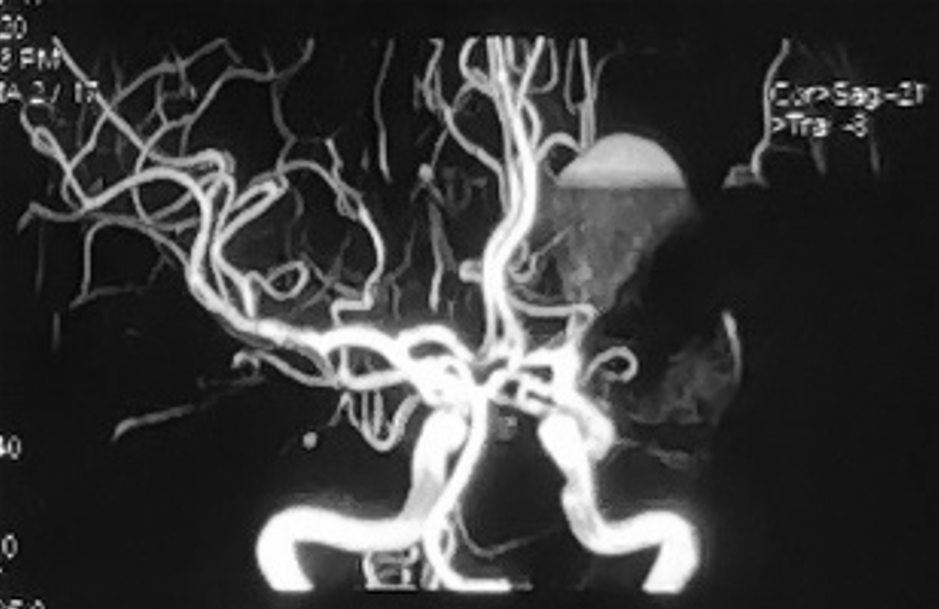

性别:女性,年龄:33 y.o

影像学阳性

术前诊断: